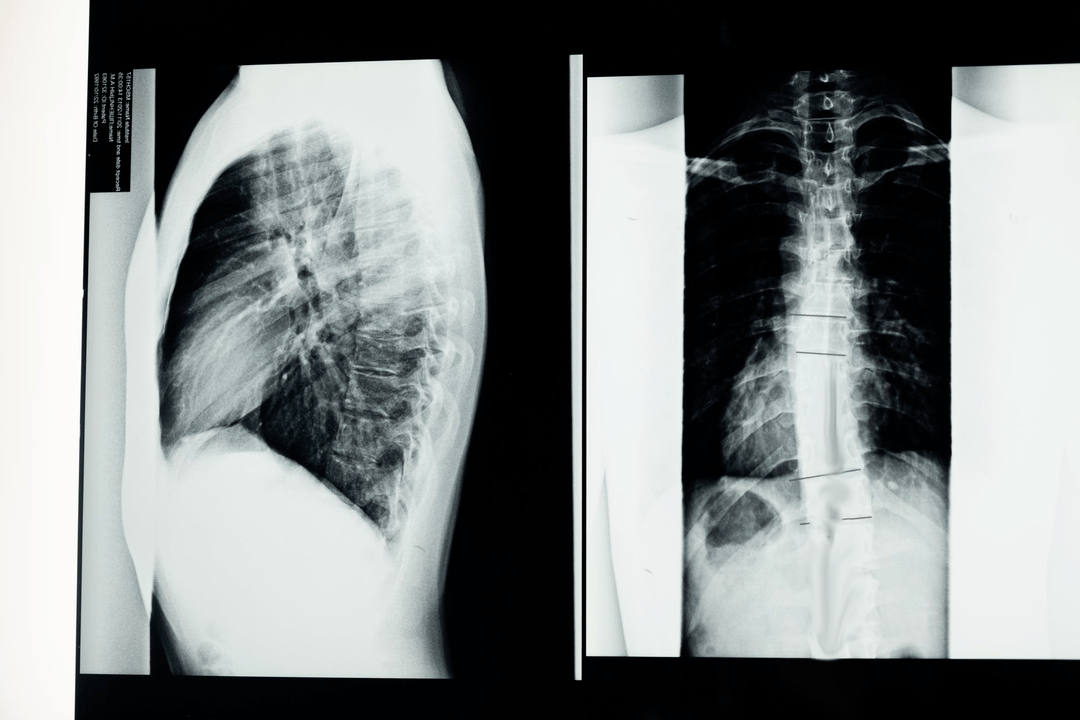

Prieš pradėdamas diagnostinius tyrimus, neurologas surenka paciento ligos istoriją ir atidžiai išnagrinėja jo skundus. Osteochondrozė turi bendrų simptomų su kai kuriomis kitomis ligomis, todėl svarbu mokėti atskirti patologijas. Osteochondrozės diagnozę patvirtinti padės rentgeno tyrimai: rentgenografija, mielografija ir kompiuterinė tomografija.

Tyrimo rentgeno nuotrauka leidžia gauti stuburo ar jo dalies rentgeno vaizdą. Tokiu būdu gydytojas gali nustatyti ligos paveiktą vietą. Aiškumo dėlei paaiškinsime, kaip osteochondrozę galima nustatyti rentgeno spinduliais: vaizde bus matomas tarpslankstelinio disko susiaurėjimas, kaulų išaugos (osteofitai) ar pakitusi stuburo segmento forma.